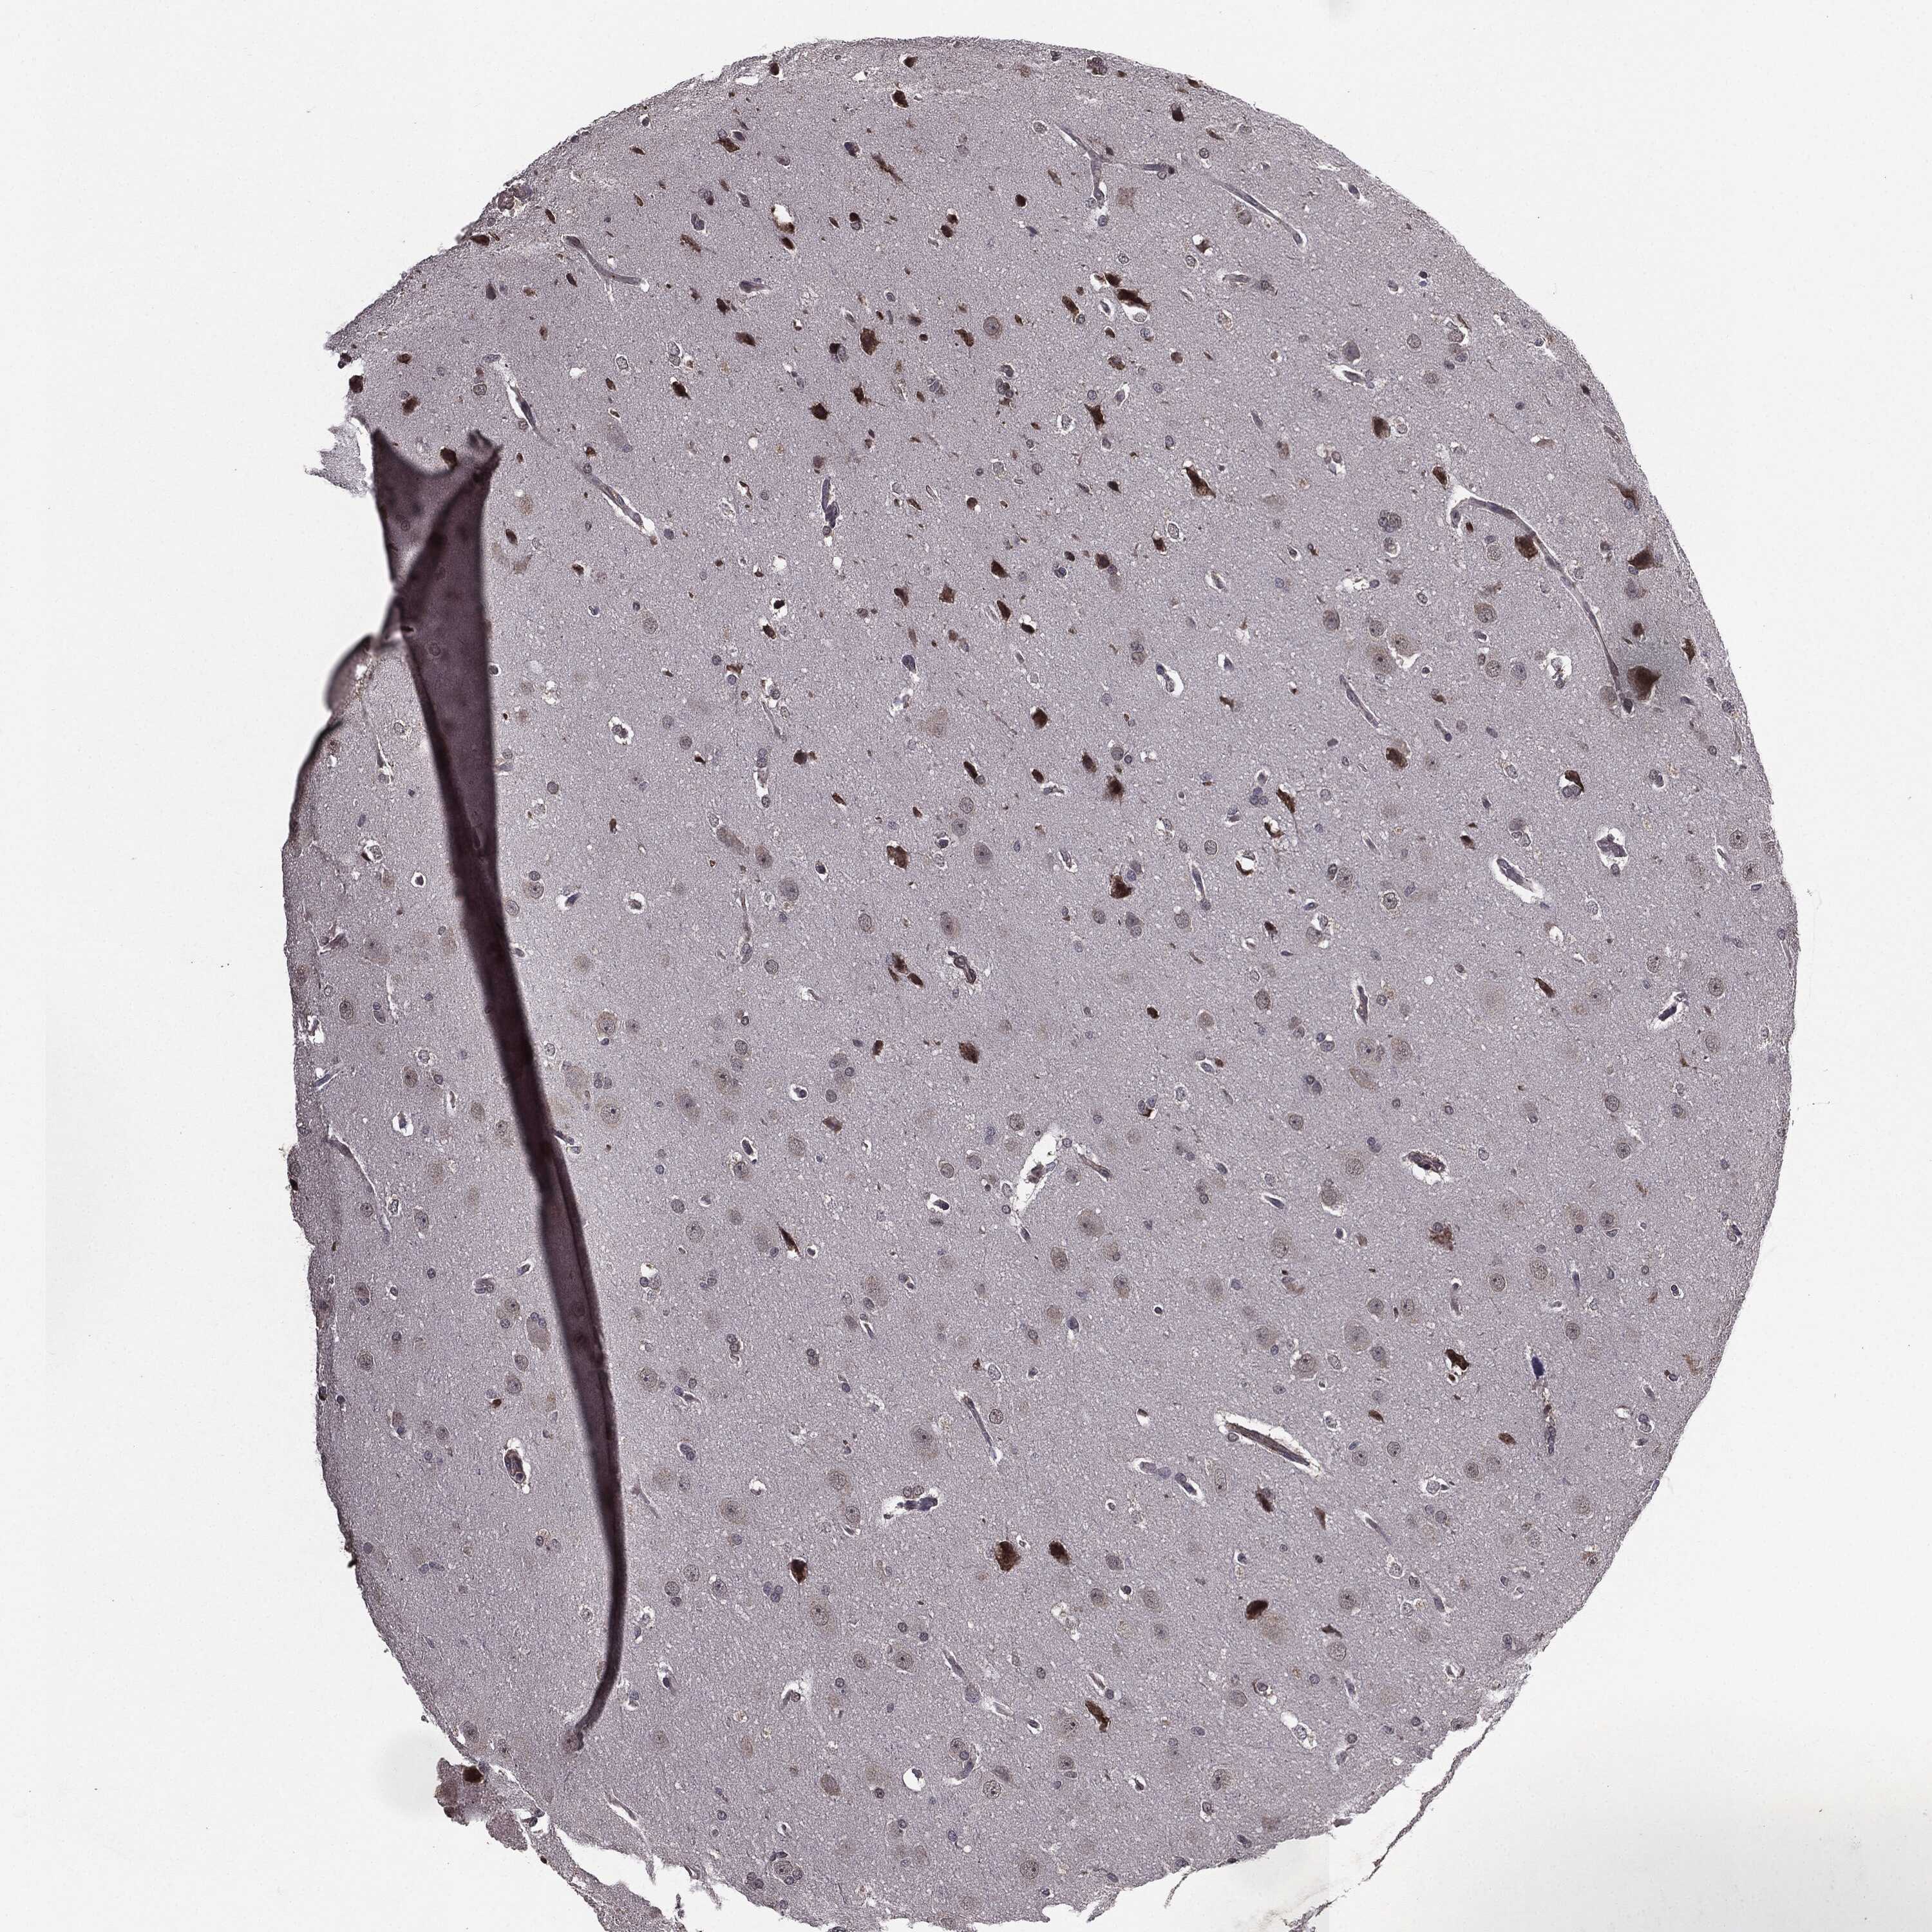

GLIOMA - Protein expressioni

A mouse-over function shows sample information and annotation data. Click on an image to view it in a full screen mode. Samples can be filtered based on level of antibody staining by selecting one or several of the following categories: high, medium, low and not detected. The assay and annotation is described here.

Note that samples used for immunohistochemistry by the Human Protein Atlas do not correspond to samples in the TCGA dataset.

Antibody stainingi

Antibody staining in the annotated cell types in the current human tissue is reported as not detected, low, medium, or high, based on conventional immunohistochemistry profiling in selected tissues. This score is based on the combination of the staining intensity and fraction of stained cells.

Each image is clickable and will lead to virtual microscopy that enables deeper exploration of all samples and also displays staining intensity scores, fraction scores and subcellular localization as well as patient and tissue information for each sample.

Antibody HPA052606

Antibody HPA077139

Staining

High

Medium

Low

Not detected

Intensity

Strong

Moderate

Weak

Negative

Quantity

>75%

75%-25%

<25%

None

Location

Nuclear

Cytoplasmic/membranous

Cytoplasmic/membranous,nuclear

Glioma, malignant, Low grade

Glioma, malignant, High grade

Glioma, malignant, NOS